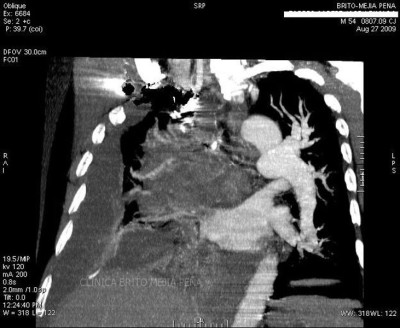

Trombosis arteria pulmonar 3D